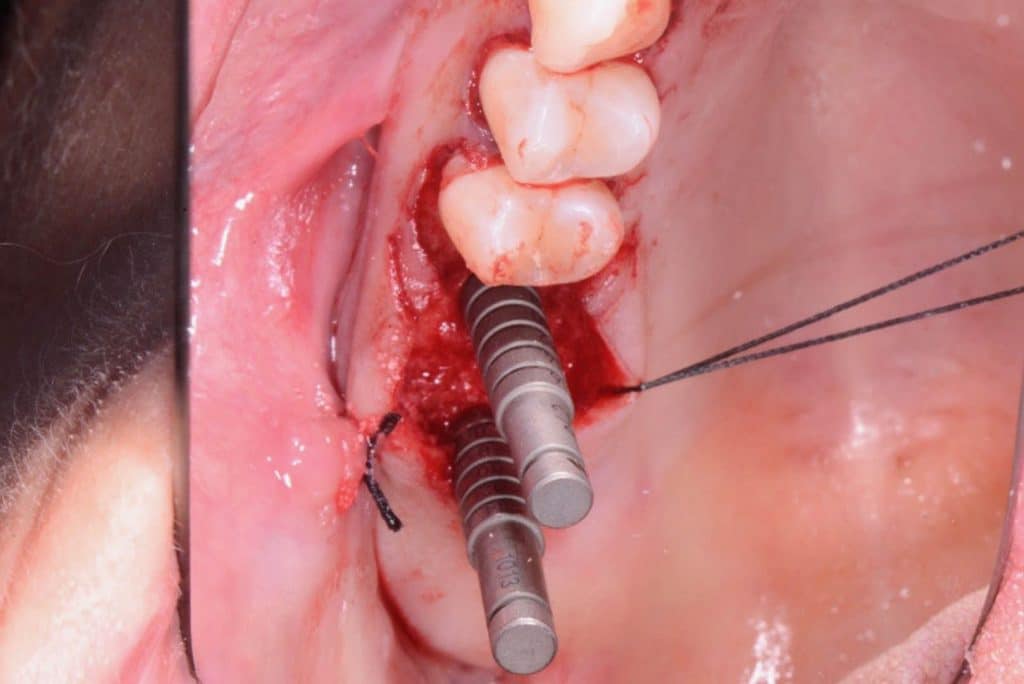

The crest is cut with a size 15 Bard-Parker scalpel, and a full-thickness flap is made performing a double widening suture both buccally and palatally. The first bur to be used is the Locator Drill that works only for 3.5 mm and only drills the cortical bone.Subsequently, I used the 1.2 mm diameter Probe Drill.

I stopped at about 2 mm from the maxillary sinus floorIn this case, since the distance between the crest and the floor is of about 8 mm in #16 area and 6mm in 17# area, a 6 mm stop is inserted on the first implant and a 4mm stop on the second.

For the next step, I used the Guide Drill. That bur only works for a depth of 2 mm and allows for the correct centring of the following bur. Then, I have used the 3mm Sincerest Drill to create precise housing to insert the SinCrest tool.

Since the bone was soft – considering I wanted to use Wide-Neck Implants – I decided to use a 4mm SinCrest on the site prepared at 3mm.

Two 8mm Straumann Wide-Neck have been inserted. After inserting a healing abutment with a height of 2 mm, a detached stitches suture was made. Good planning allowed me to be precise with the incision, and only 2 stitches have been necessary.